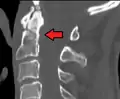

Fracture of dens

Repair of a dens fracture

Fractures of the dens, not to be confused with Hangman's fractures, are classified into three categories according to the Anderson Alonso system:

• Type I fracture - Extends through the tip of the dens. This type is usually stable.

• Type II fracture - Extends through the base of the dens. It is the most commonly encountered fracture for this region of the axis. This type is unstable and has a high rate of non-union.

• Type III fracture - Extends through the vertebral body of the axis. This type can be stable or unstable and may require surgery.